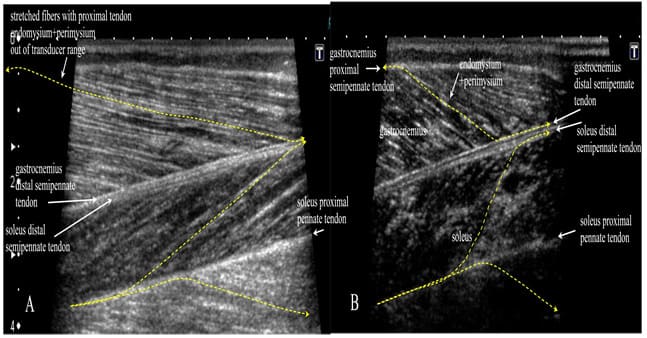

Histology-US Correlation

The whole tendinous system can be clearly visualized by ultrasound. The tendons as well as perimysium+endomysium show in a relaxed muscle as hyperechogenic lines of different thickness. Skeletal muscles show 0,1-0,4mm of anechoic space between the bright lines and that is 4 to16 myofibers (depending of the size of myofibers) per dark space between the lines of endomysium + perimysium in a relaxed state, neutral position. Figures 17,18,19 show the US images of selected muscles.